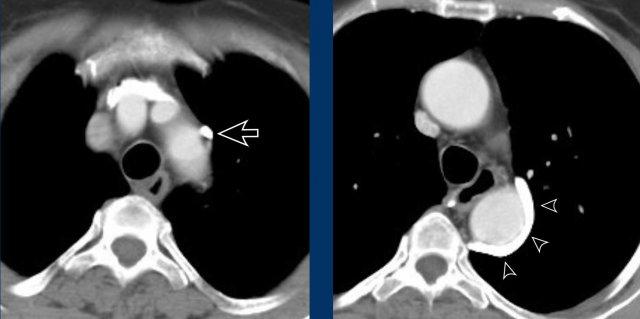

Hình ảnh

Bệnh nhân này được lên kế hoạch cắt thùy trên phải do ung thư phổi và bất thường mạch máu này ban đầu đã bị bỏ sót trên hình ảnh CT.

Những hệ quả trong phẫu thuật của bất thường như vậy nhấn mạnh tầm quan trọng của việc không bỏ sót các biến thể này.

PAPVR bên trái phát hiện tình cờ với dẫn lưu trên tim của máu từ thùy trên trái vào tĩnh mạch tay đầu trái (các mũi tên).